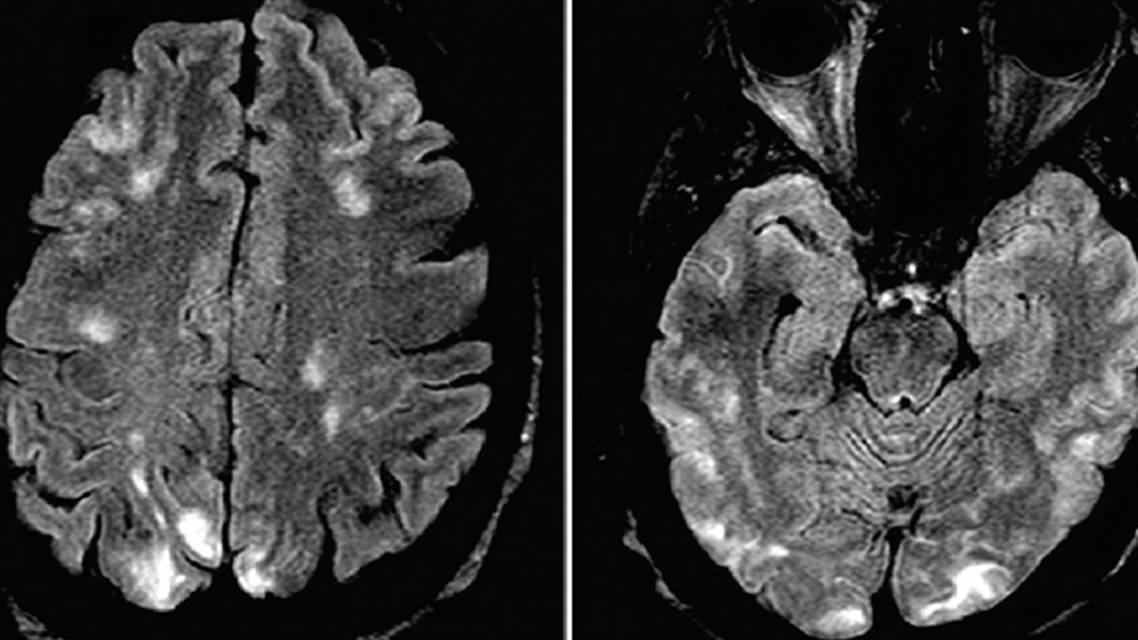

After her BP was under control, Ms. J had a brain MRI with findings of bilateral posterior-predominant multifocal nonenhancing bilateral T2 hyperintensities (Figure 1A). Initially these findings were considered indicative of posterior reversible encephalopathy syndrome (PRES) secondary to severe hypertension. Central nervous system (CNS) vasculitis associated with SLE or SS was initially low on the differential, although because of Ms. J's history of autoimmune disease, an MR angiogram (MRA) of the head was performed. The MRA findings showed normal vasculature, supporting a cause other than vasculitis for the lesions.

A repeat spinal angiogram 1 month later showed resolution of vascular abnormalities; repeat brain MRI 4 months later showed resolution of T2 hyperintensities (Figure 1B). Ms. J has remained stable since with no further vascular events over 6 months of follow-up care.

Imaging Studies. In the case presented, the initial brain MRI demonstrated bilateral predominantly posterior cerebral T2 hyperintensities thought to be diagnostic of PRES,19 which was consistent with the clinical presentation of encephalopathy and hypertensive crisis. It should be noted, however, that although PRES may be caused by hypertension, it has also been reported in the setting of rheumatological conditions including SS, even in the setting of normal blood pressure and absence of other contributing etiologies.20,21 It is interesting to note that reports of PRES in the setting of rheumatological disease typically do not include conventional angiography or brain biopsy, and therefore, a vasculitis causing such reversible MRI abnormalities cannot be ruled out. In the case presented here, because Ms. J's MRI abnormalities resolved with immunotherapy, we cannot rule out PRES, although in the presence of angiogram-proven vascular abnormalities, cerebral vasculitis is deemed much more likely.